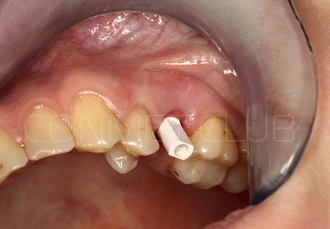

Направляющие втулки нового типа имеют цветовую маркировку (с диаметром отверстия 2,2 мм - серебристого цвета и 2,8 мм - золотистого цвета), а также одинаковый внешний диаметр, что позволяет использовать 2 одинаковых шаблона, но с втулками разного диаметра.

Характерной особенностью новых втулок является их фиксация в шаблон без использования клеев или адгезивов. Это значительно упрощает работу при фиксации втулок в шаблон и абсолютно исключает попадание фиксирующего клея внутрь втулок.

Имплантат устанавливается в подготовленное ложе. Так как не производится широкого откидывания слизисто надкостничных лоскутов и операция проводится через маленькое перфорационное отверстие, кровоточивость и сама операционная травма - минимальные.

После установки имплантата Конмет,  на период интеграции (6-8 недель), фиксируется винт заглушка. В подобных случаях швы никогда не накладываются, а пефорационное отверстие в слизистой оболочке закрывается дентальным Солкосерилом.